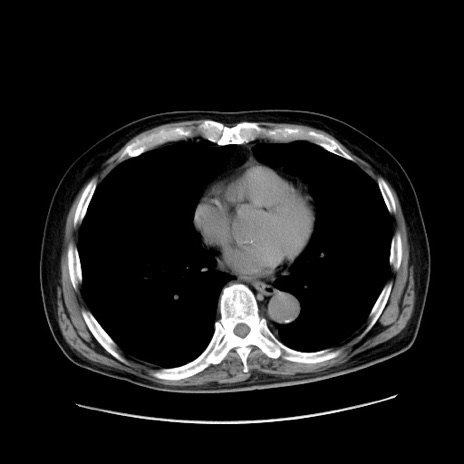

症例30(横断像)

【症例】80歳代男性

【主訴】臍周囲痛

【現病歴】約6時間前から臍下部痛が出現。次第に腹部膨隆・背部痛も生じてきたため来院。背部痛の場所は変化しない。

【身体所見】意識清明、BT 36.3℃、BP  131/87mmHg、P 87bpm、SpO2 100%(RA)、臍周囲自発痛・圧痛あり、反跳痛なし、自発痛部位に一致して板状硬あり、腹部膨隆、腸雑音減弱、CVA tenderness両側陰性。